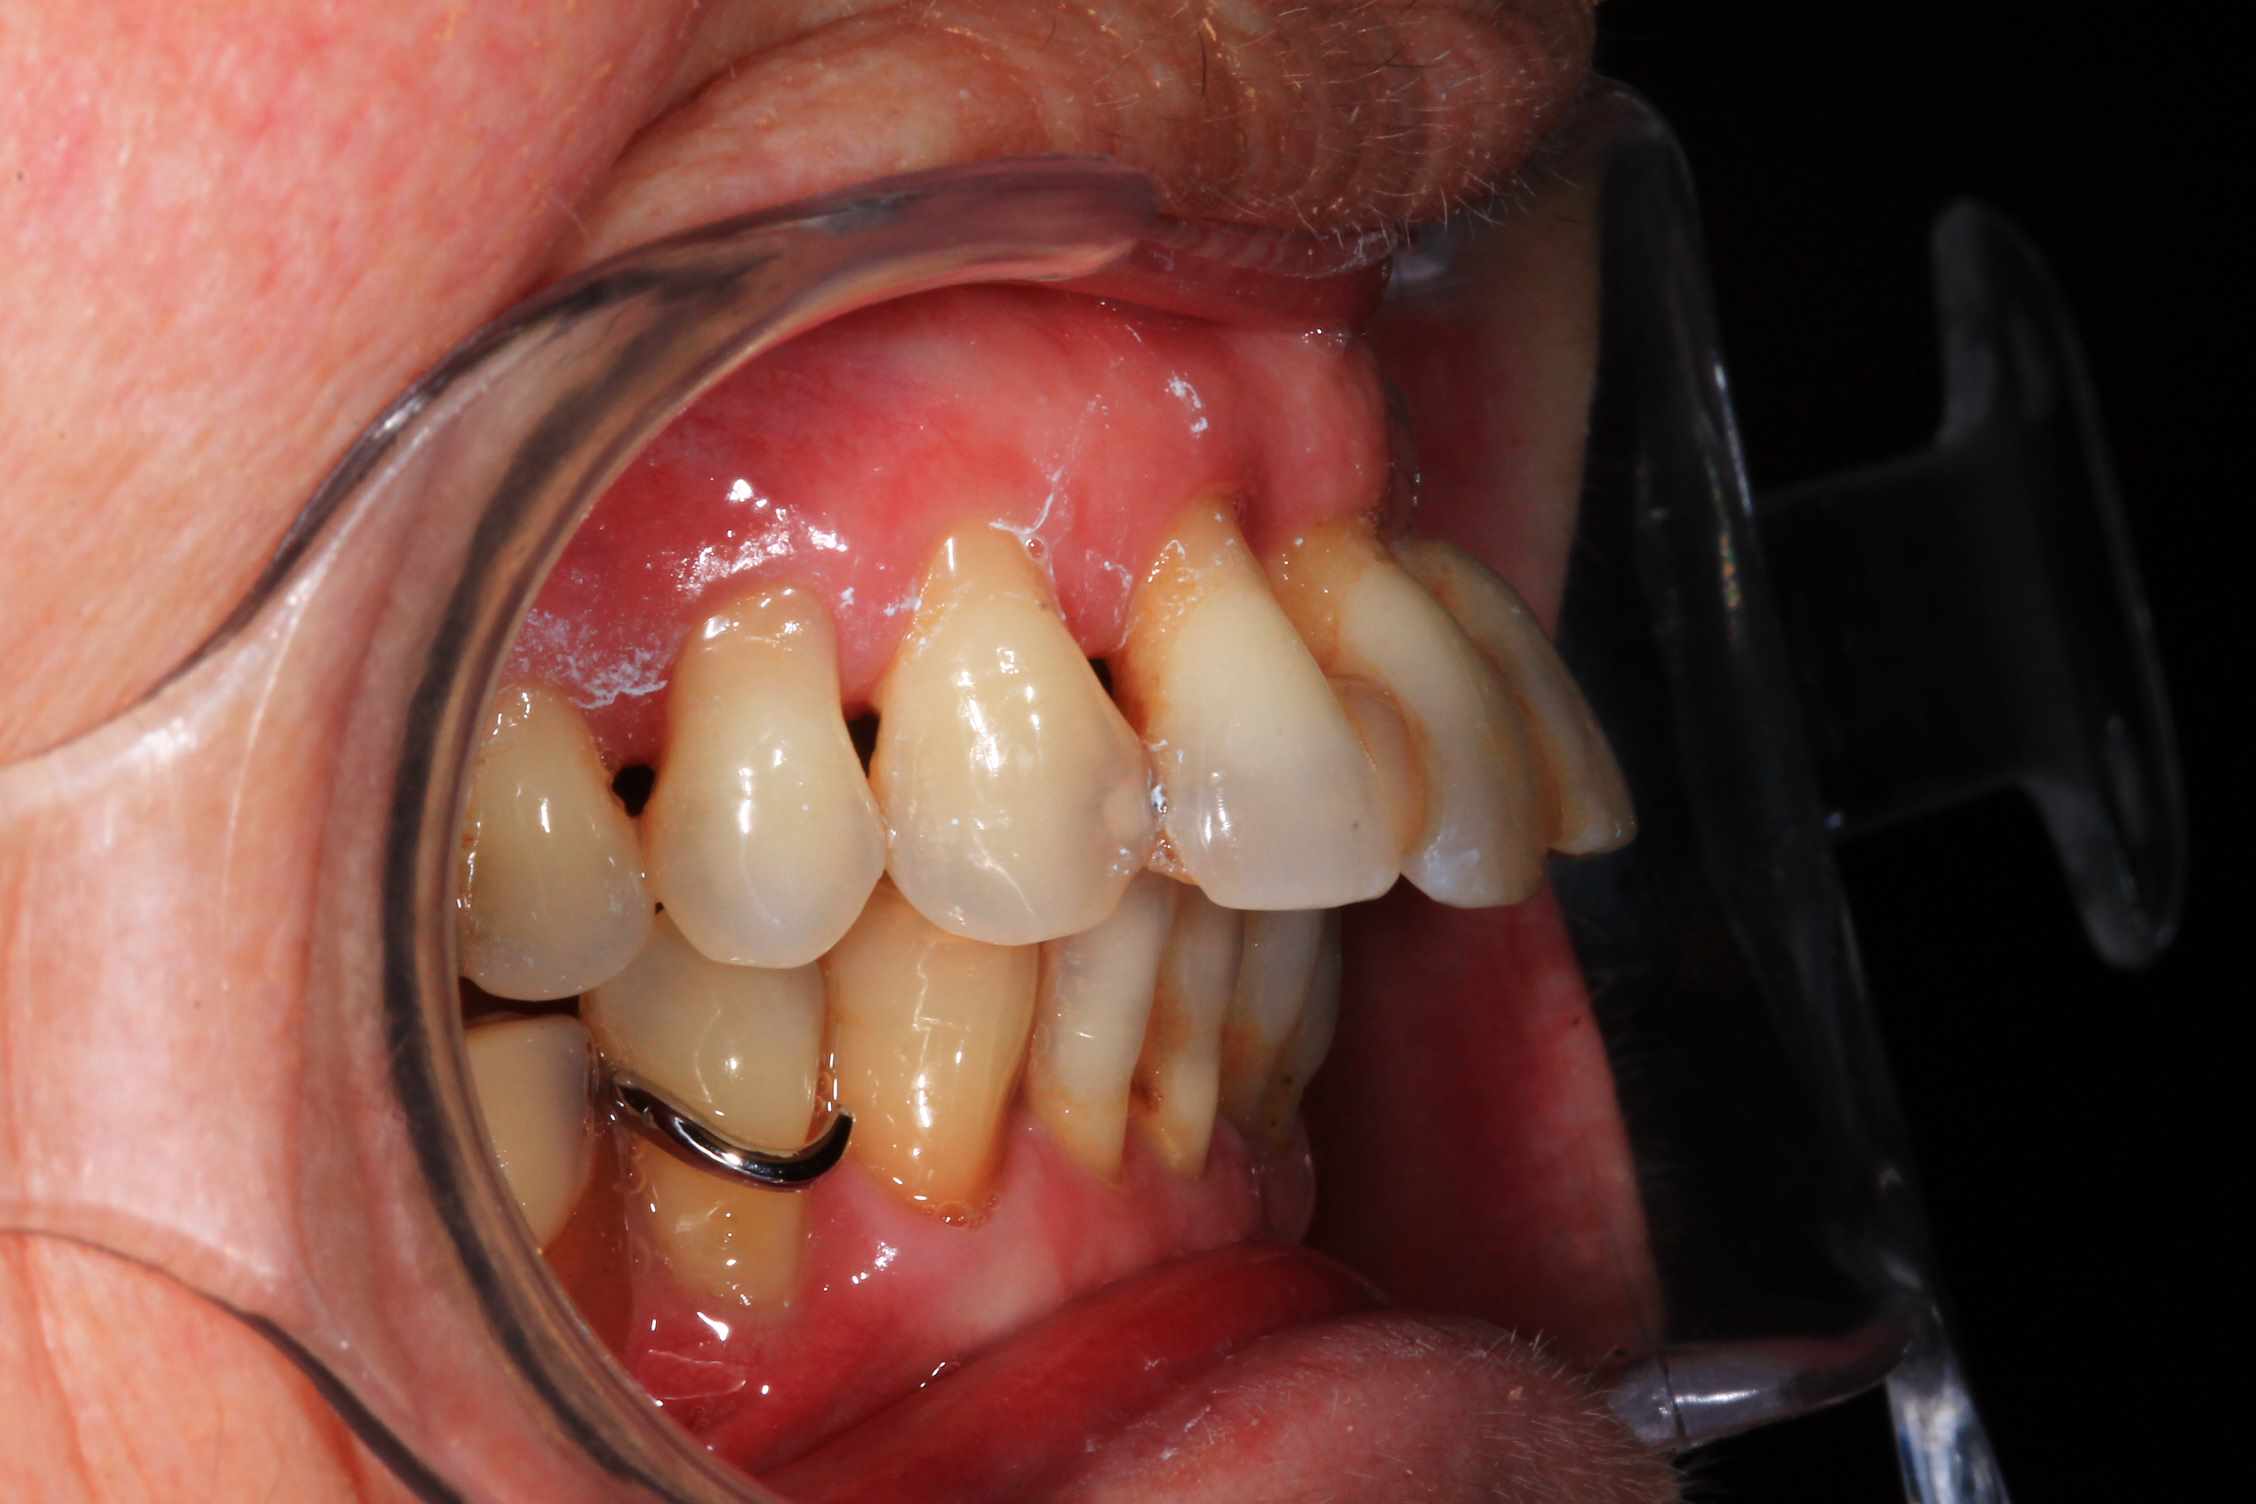

les 4 incisives sup sont à bout de souffle . Planification et export du guide résine avec blueskyplan. Export du modèle osseux et simulation de la chirurgie, comme d'hab selon mon protocole.

Quand les implants sont peu nombreux et proches, un guide résine est suffisant. C'est alors beaucoup plus rapide.

Pré-op :